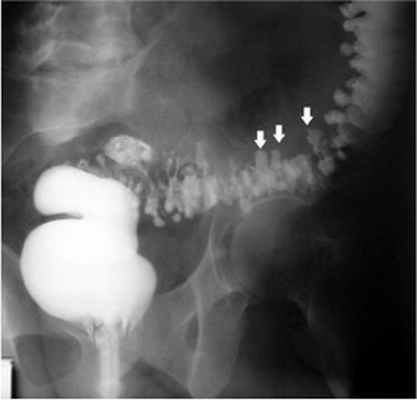

- Ирригоскопия - рентгеновское исследование, при котором производят наполнение просвета толстой кишки контрастной взвесью и оценивают ее состояние при наполнении и после опорожнения кишки.

В диагностике заболевания вне осложнений наиболее ценными являются рентгенологические (ирригоскопия с ирригографией) и эндоскопические (ректороманоскопия, колоноскопия). Таким образом, возможность проявления тяжелых осложнений требует своевременной диагностики и лечения дивертикулярной болезни.

Клинические проявления дивертикулеза толстой кишки и его осложнений не могут служить основанием для установления точного диагноза заболевания. Диагностика и дифференциальная диагностика дивертикулеза толстой кишки основывается на анализе клинических проявлений заболевания и результатах обязательного рентгенологического и эндоскопического исследований толстой кишки.